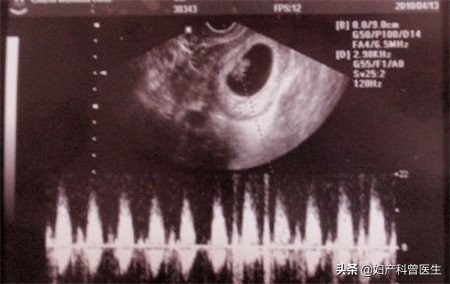

第一次:停经约6-8周

大概是停经50天左右,检查孕囊的情况(宝宝居住的"房子"),查看胚芽大小可推测孕周,如有胎心管搏动,就表示小生命有心跳了。早孕超声还有一个重要的目的就是确定是否为宫内妊娠,排除宫外孕及葡萄胎,查看单胎还是多胎。

孕囊:宝宝居住的"房子"